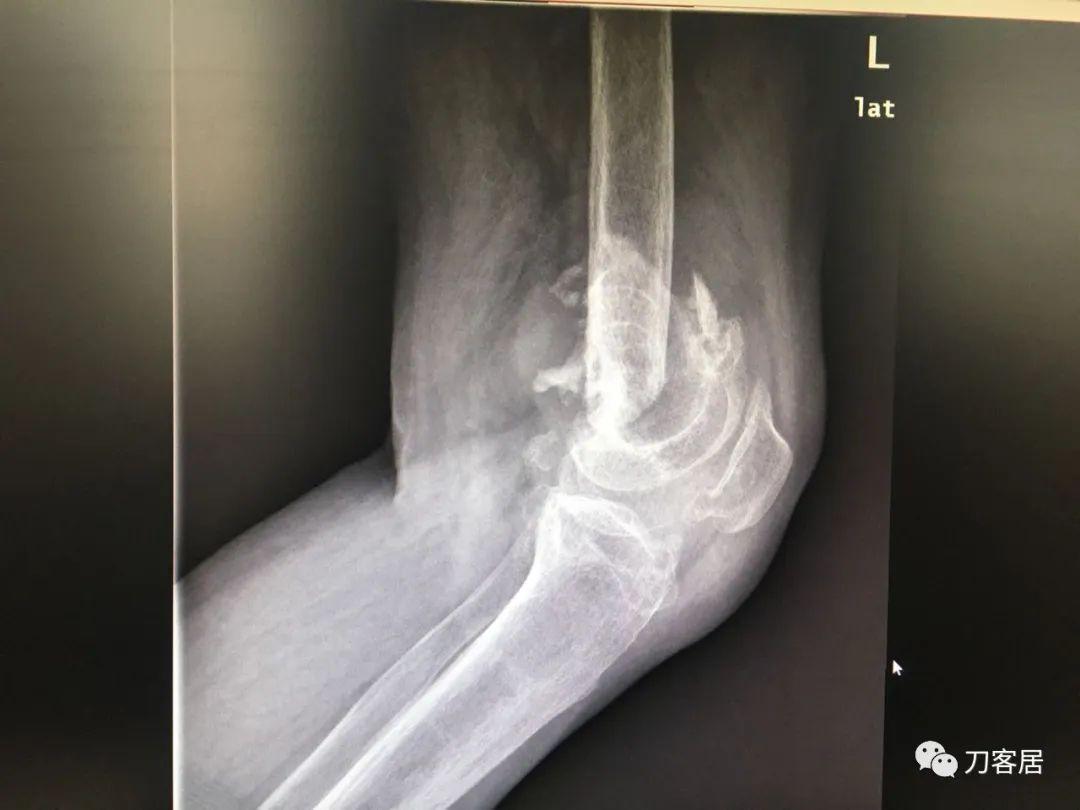

我不是中医黑2: 股骨髁上骨折,中药外敷治疗致股骨髁上陈旧骨折,县级中医医院手术,骨折病例用了骨肿瘤手术关节置换假体。

摘要: 这个病例第一次是摔伤致股骨髁上骨折,不知何种原因患者家属要求保守治疗,外包中药处理后骨折未愈合骨不连,后到一个县级中医院行了关节置换,选择的是肿瘤型假体。

然后变成了陈旧性骨折不连接,然后做了骨肿瘤假体的膝关节置换,这个假体是不是骨肿瘤假体,我说的不一定准确,但我觉得这种手术方式,应该是骨肿瘤医生的手术方式,一般的正规关节外科大夫,不应该做成这个样子。

风吹麦浪10:45AM这个病例第一次是摔伤致股骨髁上骨折,后不知何种原因家属要求保守治疗包中药处理后骨折未愈合骨不连,后到一个县级中医院行了关节置换,选择的是肿瘤型假体。

现术后2年摔倒后致假体周围骨折。

何川2:58PM我是坚决反对这种病例一期做置换。如果,实在要做假体,要做好精细严密的术前计划,这是骨折病例,不是肿瘤,那些碎掉的骨块完全可以利用起来,延长杆就不需要用很长了。

从X片看没有涉及副韧带止点,可以保留重要骨块,加内固定钢板辅助,非限制性假体即可,实际用了铰链、这么长的杆,全髓腔骨水泥,基本打定主意一锤子买卖,把自己后路全断了。